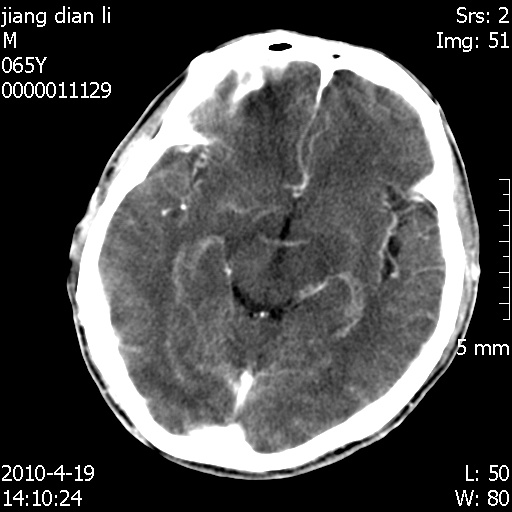

老年男性,突发左下肢无力1天,其余有价值的检查都没有。平扫ct值大约60hu,增强后ct值没什么改变,请大家讨论一下这个病例是什么?说明诊断理由。

左小脑、右大脑顶叶多发圆形高密度病灶,其周环状低密度影。考虑多发脑出血。隔期观察。

至于是出血还是微小钙化所致的高密度无法考证,三个都出血也不是一点都不可能,同一种组织学类型的肿瘤受到同一个外来的因素影响后会表现出相同的病理变化。说实在的,我本身支持转移瘤的,就是想不通为什么不强化?我认为单纯脑出血的边缘不会那么光滑,并且那也不是出血的常见部位,多发也不常见。

刚刚复习了转移瘤的不典型ct征象,有4条,分享给大家:

1、高密度灶:多为瘤内有较多沙粒体钙化所致,而不是出血,ct值可高达95hu;

2、无强化;

3、无水肿;

4、无占位效应。